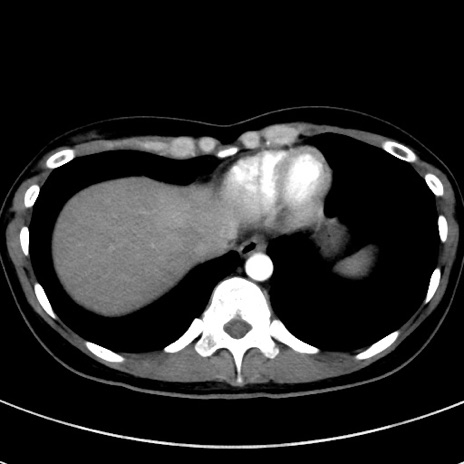

症例17(横断像)

【症例】20歳代女性

【主訴】嘔吐、下腹部痛

【現病歴】昨日夕食後に嘔吐し下腹部痛が出現。本日になっても嘔吐持続し改善しないため来院。

【身体所見】意識清明、BT 37.2℃、BP 108/67mmHg、腹部:平坦、やや硬、下腹部正中から右にかけて圧痛あり、反跳痛軽度あり、tapping pain(+)。

【データ】WBC 13600、CRP 14.94